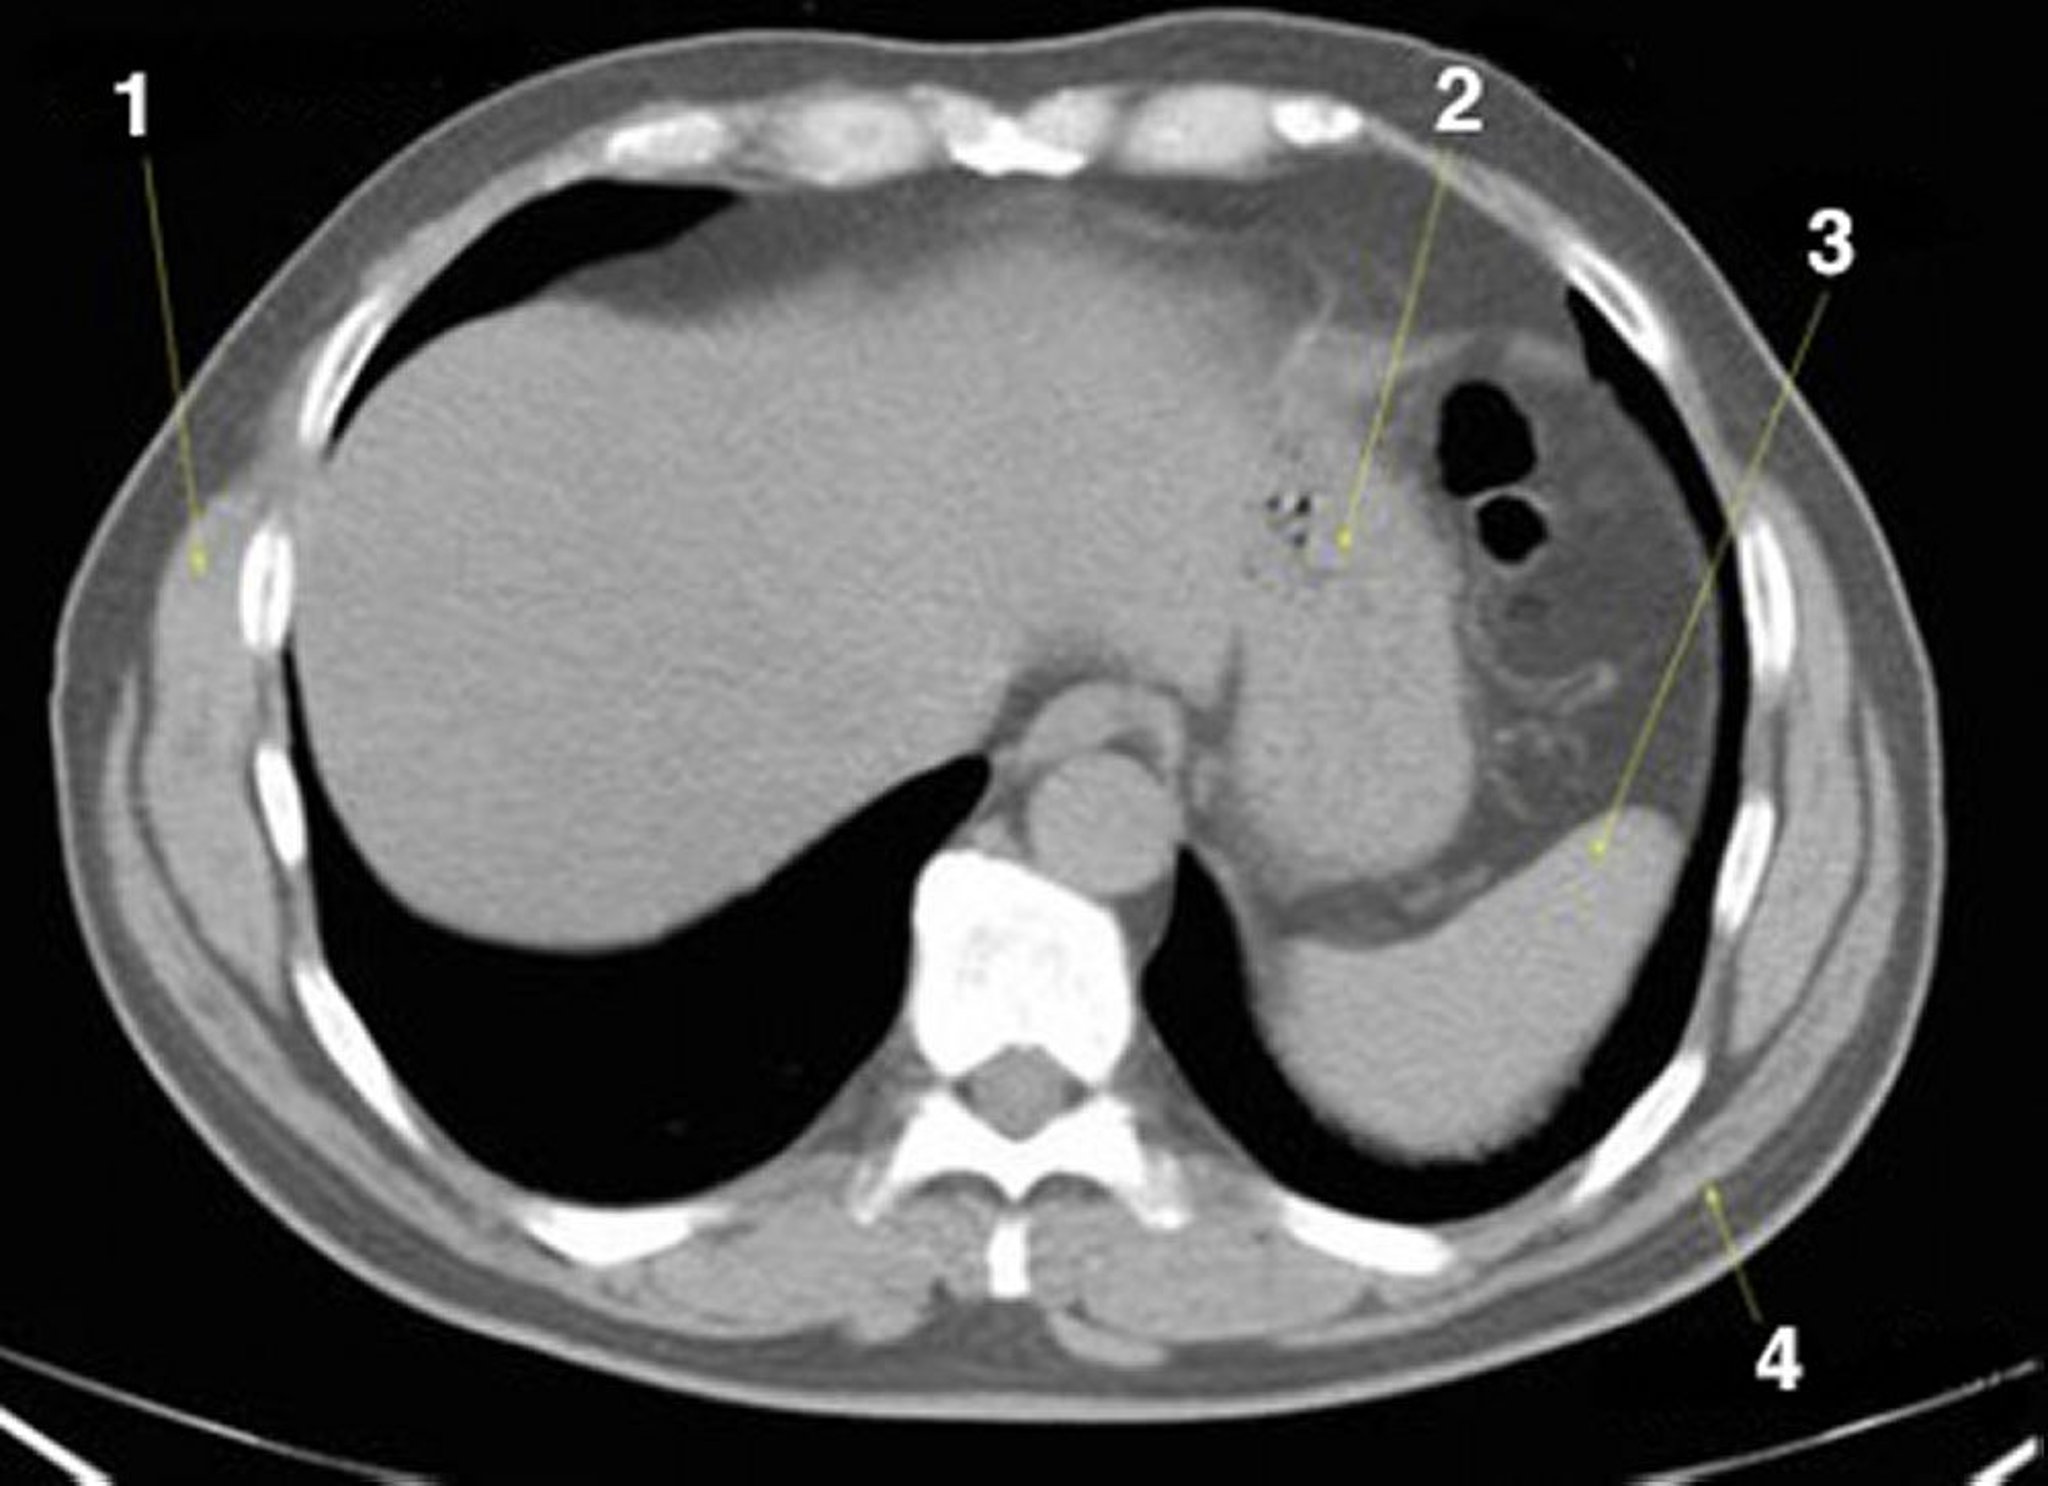

КТ брюшной полости и таза без контраста, демонстрирующая нормальную анатомию (слайд 2)

1 = передняя зубчатая мышца; 2 = желудок; 3 = селезенка; 4 = широчайшая мышца спины.